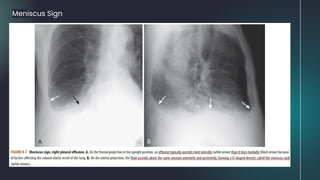

Meniscus Sign

Effect of Patient positioning